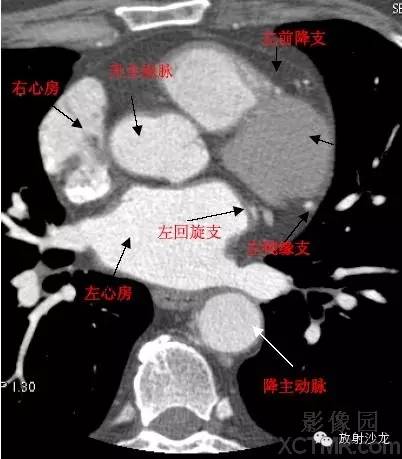

心脏冠状动脉CT解剖中文详细标注

LA -Left Atrium左心房

RA -Right Atrium右心房

D. Aorta-Descending Aorta降主动脉

LAD -Left Anterior Descending Artery左前降支

LCX -Left Circumflex Artery左回旋支

LMB -Left Obtuse Marginal Branch 左边缘支(钝缘支)

RCA -Right Coronary Artery 右冠状动脉